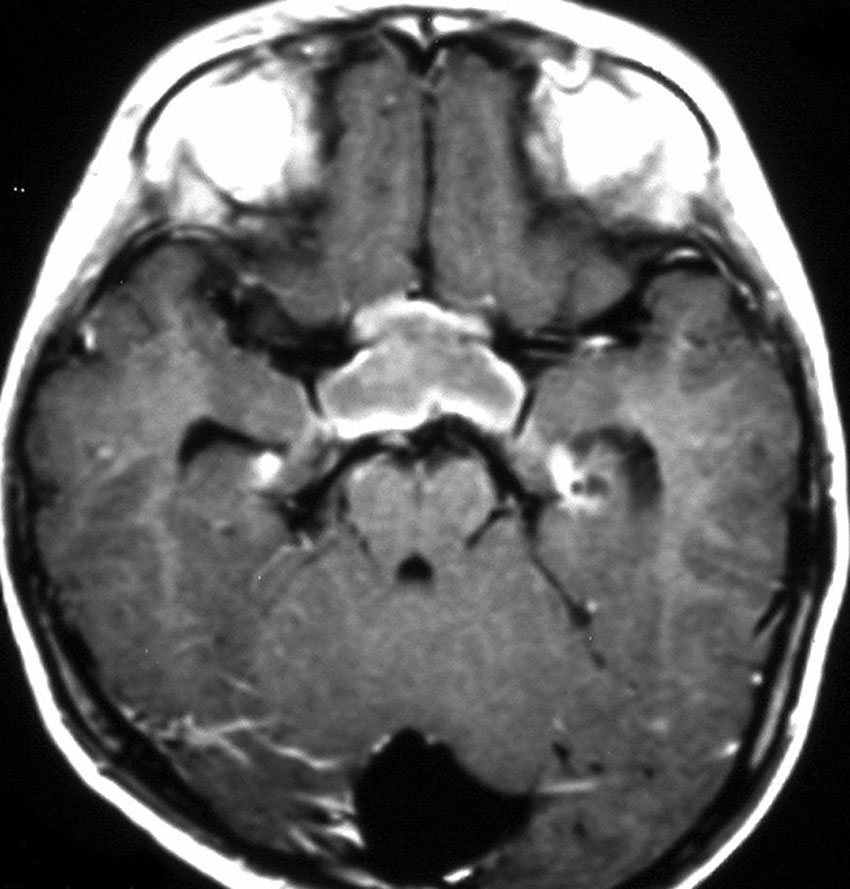

化学療法が有効なのは,上の画像のようにガドリニウム増強で強く増強されるタイプです,またT2強調画像で強い高信号になるものほど化学療法が有効です,要するに毛様粘液性星細胞腫の要素に化学療法が有効であるということです

この毛様細胞性星細胞腫はガドリニウムでほとんど増強されません(右側のMRI)から,化学療法を行っても小さくなりませんので,手術摘出する必要があります,実際に視床下部から発生したもの視交叉が犯されておらず,手術亜全摘出できました